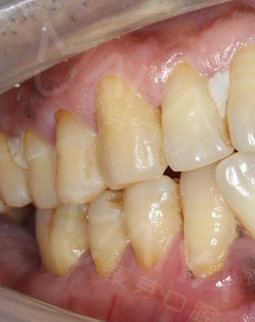

我来自广州,是一名外科医生。平时忙于工作,对口腔这方面涉及较少,长期不注意口腔卫生,刷牙不彻底,5年前,右下一颗大牙患上了根尖周炎。有的时候喝口水都牙疼,更别说吃东西了,可由于工作太忙始终忍着疼痛迟迟未就医,后来痛到实在难以忍受,就医后,医生陆陆续续为我做了几次根管治疗,但是后续未积极配合医生治疗,导致大牙崩坏,直接拔掉了。

缺牙后,不痛不痒的就更不在意了,每次吃饭都用左侧咀嚼,这一吃就是5年,时间一长,我发现一侧面部逐渐塌陷变形,周围人说我比同龄人要苍老许多,不仅影响了我的健康,更影响了我的职业形象。作为一名医护人员,我非常注重自己的仪容仪表,以饱满的精神状态接诊患者,让患者放心,给患者信息是我的职责。

拍了片子,医生指出牙周膜增宽,左上根尖部阴影大,面部有稍微萎缩,为我制定了数字化精确种牙技术,其实也很好奇,现在种牙到底有多精确多快速,和医生约定好了时间,下次直接种牙。